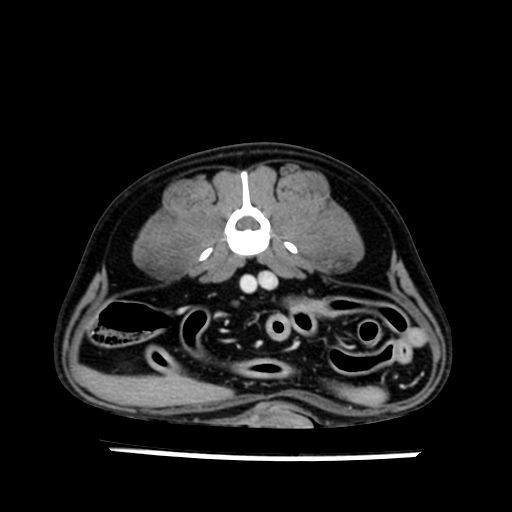

prescritto esame TAC

sequenza immagini limitata al fegato reni e surreni

le immagini ecografiche rispetto alla tac datano circa 7 mesi prima ,le surrenali sono normali nonostante il test acth sia risultato positivo .all’esame TAC dopo diversi mesi risultano aumentate armonicamente nel volume e si individua un forte sospetto di adenoma ipofisario .

sospetto adenoma ipofisario vs. meno probabilmente meningioma della base; intertiziopatia polmonare; lesione espansiva epatica, verosimilmente del lobo laterale sinistro, di sospetta natura neoplastica; lesioni spleniche di natura da definire; iperplasia/ipertrofia delle ghiandole surrenali, bilateralmente; vertebra di transizione del rachide toracico; tenosinovite cronica del muscolo bicipite brachiale di destra.